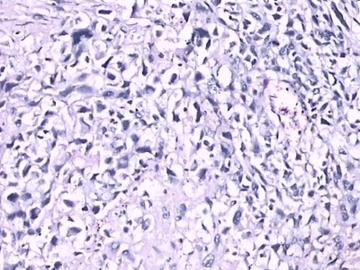

穿孔是由伤寒沙门菌感染引起肠壁坏死、穿孔,是伤寒的严重并发症之一,多见于伤寒病程第2~4周,好发于回肠末端。多见于夏秋季节,高发年龄为20~40岁,可呈暴发性流行。病因为伤寒沙门菌感染,使得肠道淋巴结组织增生、坏死、穿孔。患者多有不洁饮食病史或伤寒患者接触史。在持续高热、腹痛、腹胀、便秘或

腹泻

、肝脾肿大基础上突发腹痛加剧,以右下腹为重,随后出现明显腹胀伴冷汗、脉搏增快、体温与血压下降。肠伤寒穿孔的治疗原则:一经确诊,立即手术治疗,辅以药物及支持治疗。肠伤寒穿孔如果不及时治疗,可发生

病因为伤寒沙门菌感染,使得肠道淋巴结组织增生、坏死、穿孔。